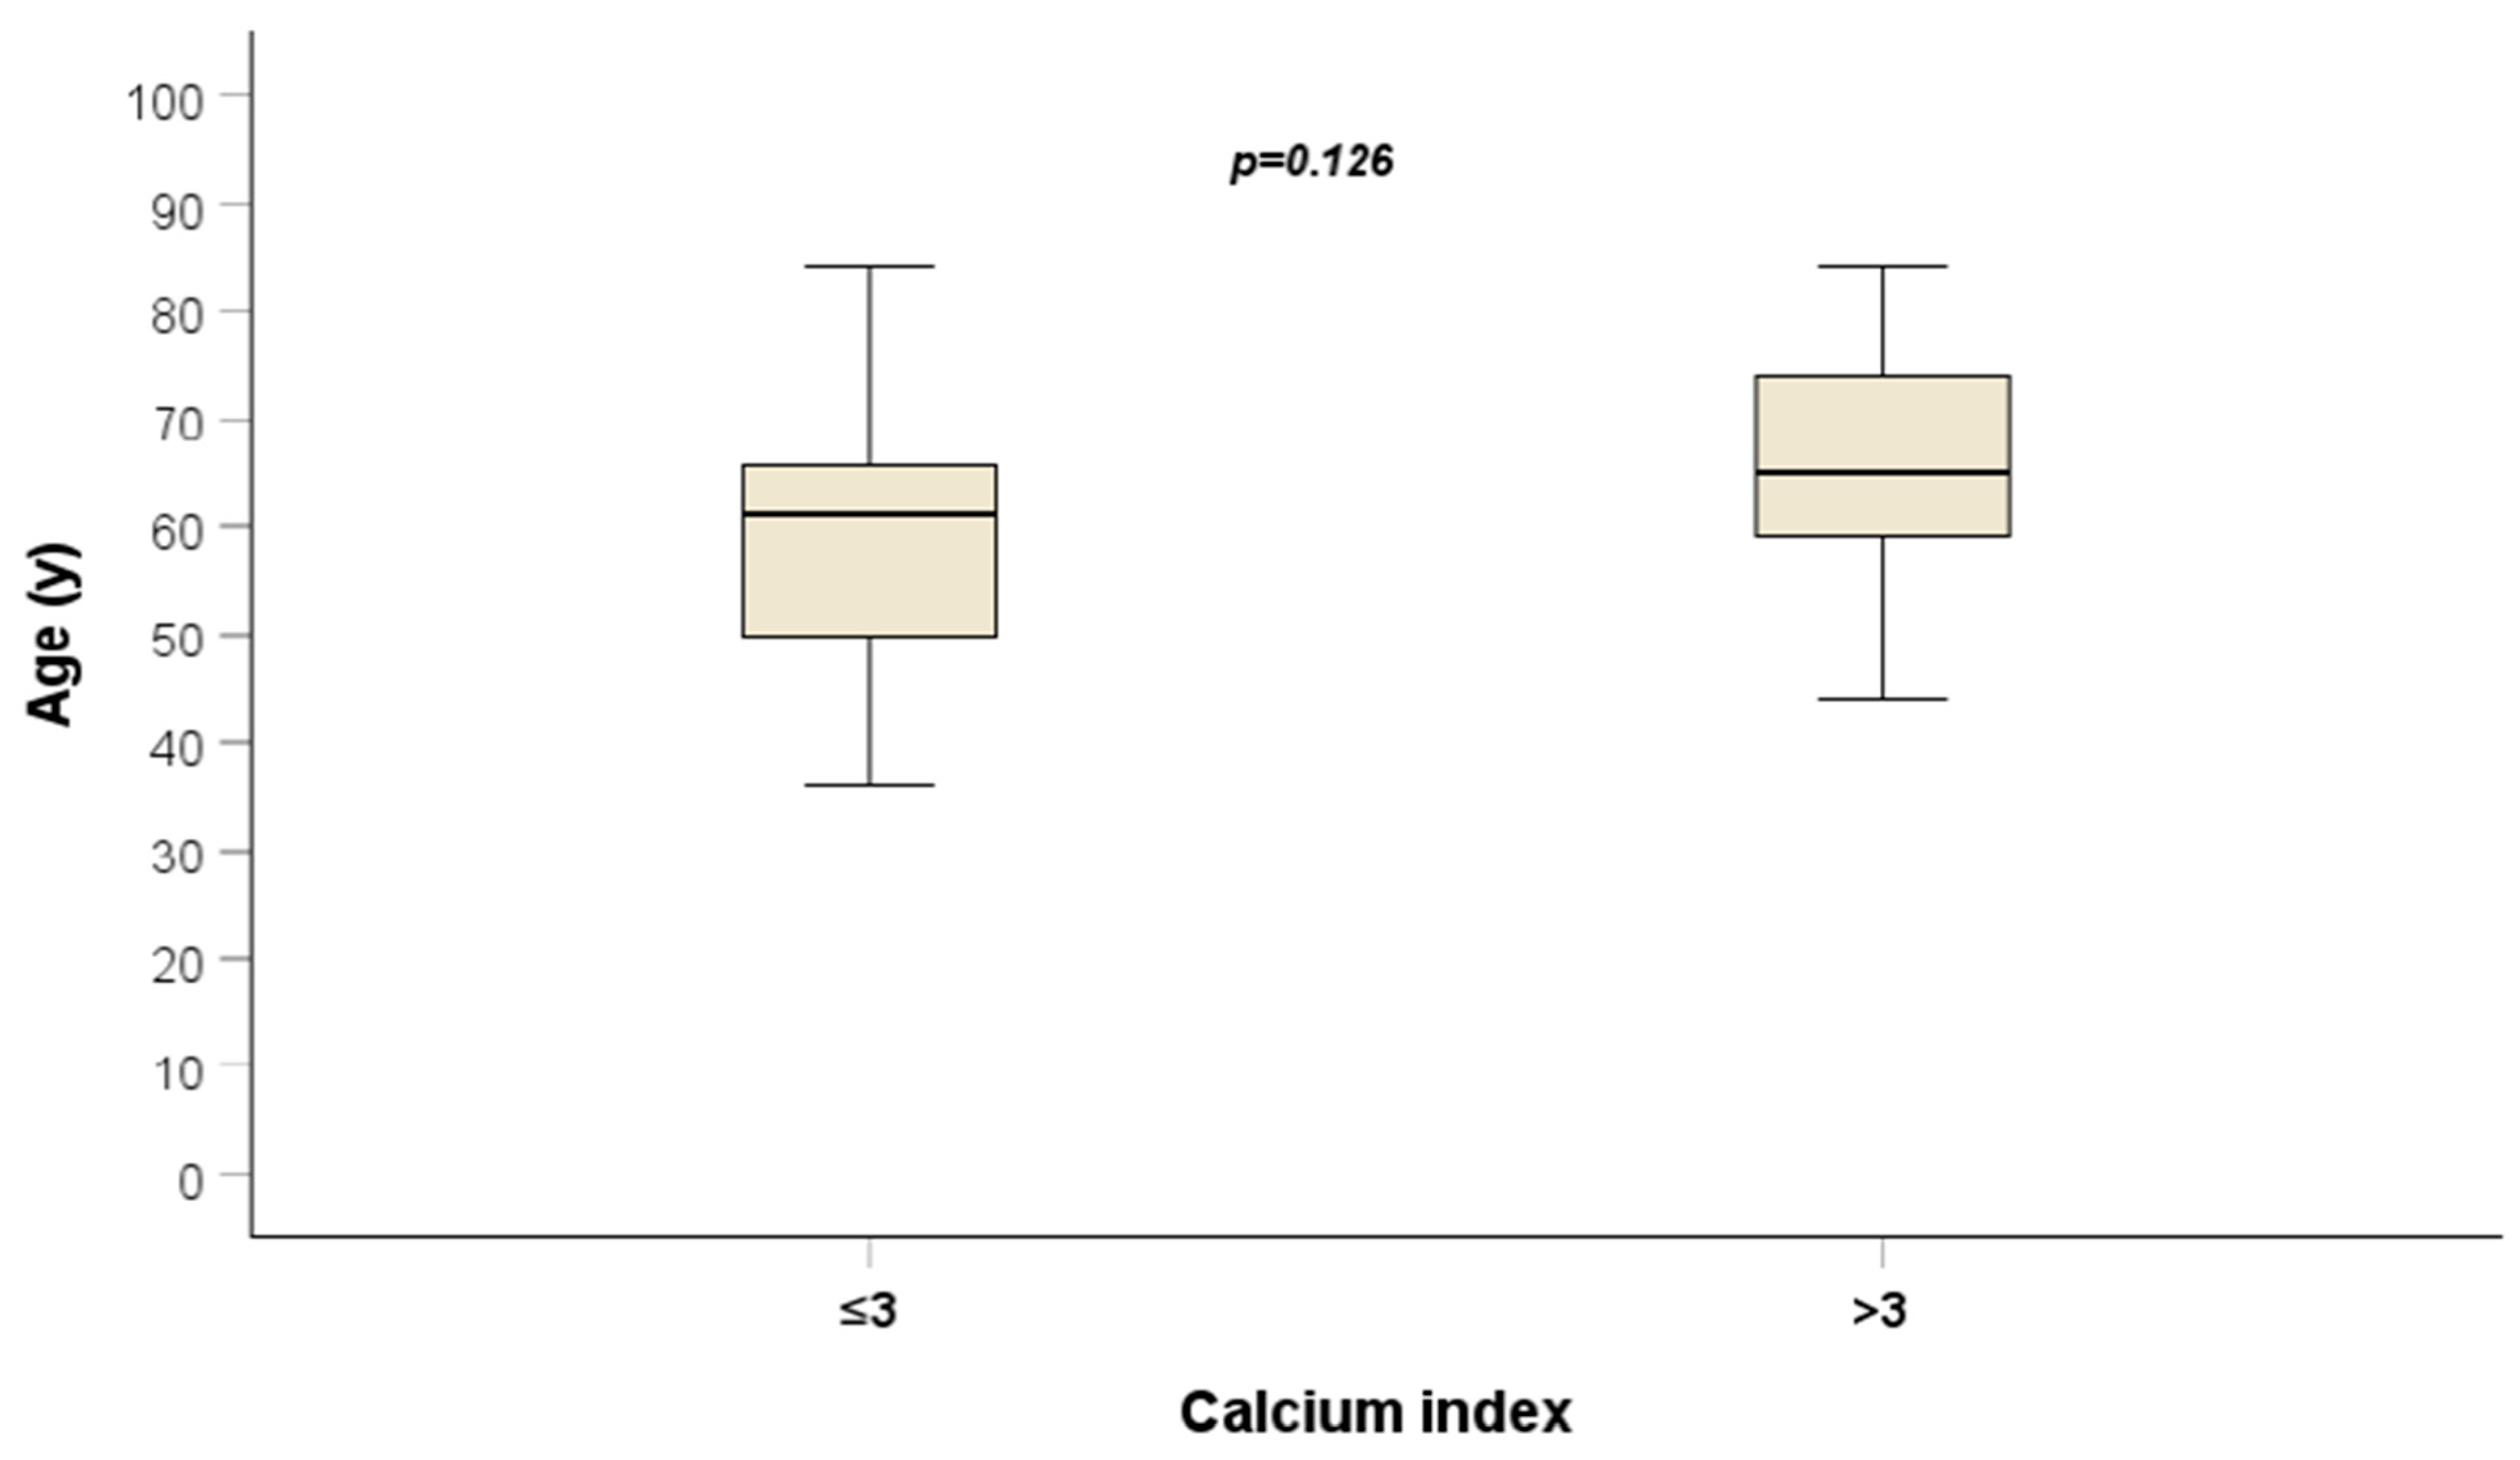

| Age | 0.019 | 1.019 (0.991–1.048) | 0.186 | |||